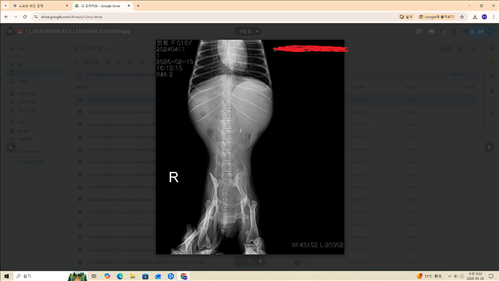

BUN/CREA 12.5 31.8 80.3 HIGH 피검사수치랑 엑스레이 사진입니다. 복수인지 가스인지 궁금하구요 전반적으로 어떤상황인지 궁금해요